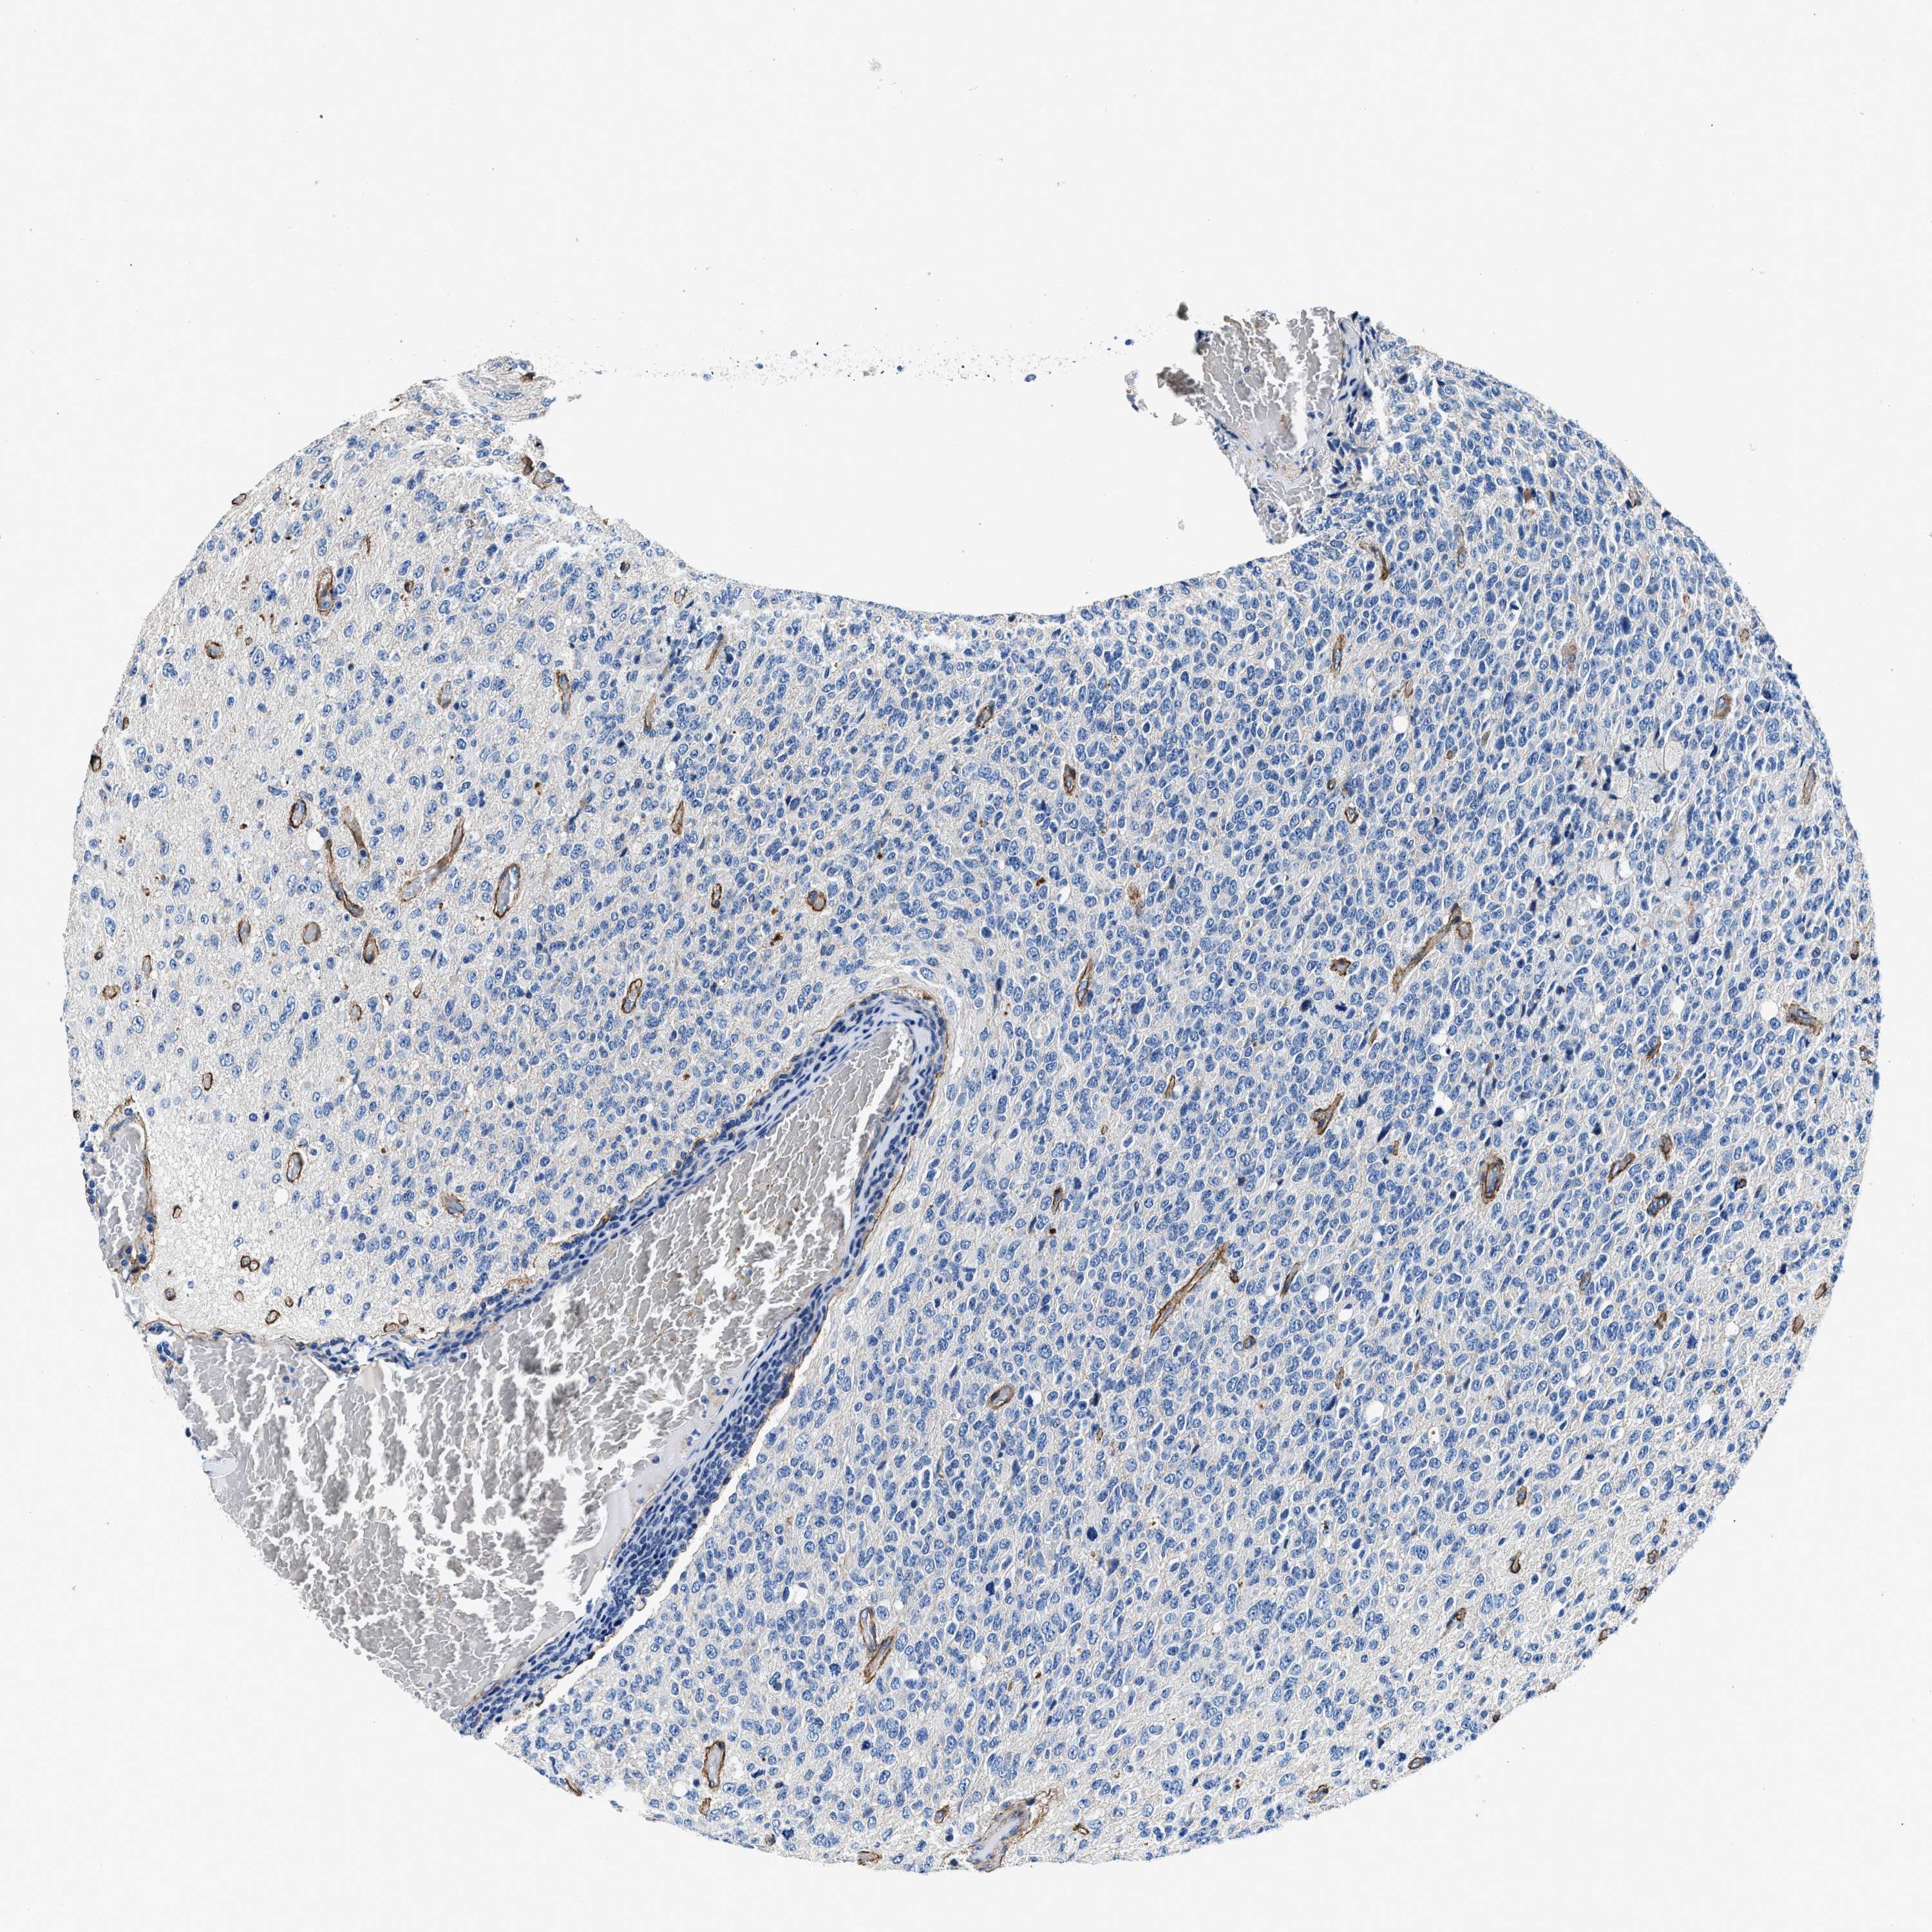

GLIOMA - Protein expressioni

A mouse-over function shows sample information and annotation data. Click on an image to view it in a full screen mode. Samples can be filtered based on level of antibody staining by selecting one or several of the following categories: high, medium, low and not detected. The assay and annotation is described here.

Note that samples used for immunohistochemistry by the Human Protein Atlas do not correspond to samples in the TCGA dataset.

Antibody stainingi

Antibody staining in the annotated cell types in the current human tissue is reported as not detected, low, medium, or high, based on conventional immunohistochemistry profiling in selected tissues. This score is based on the combination of the staining intensity and fraction of stained cells.

Each image is clickable and will lead to virtual microscopy that enables deeper exploration of all samples and also displays staining intensity scores, fraction scores and subcellular localization as well as patient and tissue information for each sample.

Antibody CAB001960

Antibody CAB016353

Staining

High

Medium

Low

Not detected

Intensity

Strong

Moderate

Weak

Negative

Quantity

>75%

75%-25%

<25%

None

Location

Nuclear

Cytoplasmic/membranous

Cytoplasmic/membranous,nuclear

Glioma, malignant, High grade

Glioma, malignant, Low grade